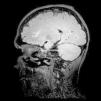

A 19-year-old male presented with asthenia, abdominal pain, vomiting, fever, jaundice, and rash. The patient quickly progressed to severe shock, purple lower limbs and toes necrosis. The diagnosis of Rickettsia spp (gene regions surveyed gltA (TaqMan) and internal control of the human RNAse P reaction) was made by PCR (polymerase chain reaction) of serum sample. Serial serology, with indirect immunofluorescence, also turned out positive with increasing IgG titers, initially <1/64 and then >1/256 two weeks later. The patient went on to present nystagmus and conjugate eye deviation. Magnetic resonance imaging (MRI) identified: multiple foci of marked hypointensity on susceptibility weighted imaging (SWI), evidenced in the corpus callosum, deep white matter, bilateral basal ganglia, thalamus and middle cerebellar peduncles, compatible with hemosiderin deposits, possibly petechial hemorrhages (Fig. 1). Foci of hyperintensity were observed on T2/FLAIR weighted images in the semiovale centrum, deep white matter and periventricular regions (Figs. 2 and 3). The patient was treated with chloramphenicol but progressed with extremity necrotic lesions, requiring bilateral transmetal amputation of toes and at the proximal phalanx of second, third, fourth, and fifth fingers of the right hand. He was discharged after 55 days of hospitalization for outpatient follow-up.

Magnetic resonance axial SWI (Susceptibility weighted imaging), at the level of the basal ganglia, shows multiple hypointense foci suggestive of petechial hemorrhages or possibly microthrombi in the white matter (subcortical and within the corpus callosum) and internal capsules and basal ganglia.